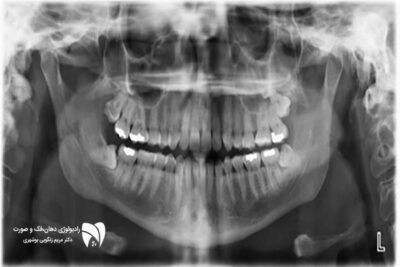

در رادیولوژی فک و صورت، تصویربرداری خارج دهانی یکی از ابزارهای اصلی برای بررسی مشکلات پیچیده است. این روش به دندانپزشکان و جراحان فک کمک می‌کند تا نمای کاملی از فک‌ها، سینوس‌ها و مفاصل فک تهیه کنند. تصاویر پانورامیک، سفالومتریک و CBCT از جمله روش‌های تصویربرداری خارج دهانی هستند که هرکدام کاربردهای خاصی دارند.

تصویربرداری پانورامیک یکی از انواع تصویربرداری خارج دهانی است. این روش امکان مشاهده کل فک بالا و پایین، دندان‌ها، مفاصل فک و سینوس‌ها را در یک تصویر فراهم می‌کند. پانورامیک برای بررسی ناهنجاری‌های ساختاری، دندان‌های نهفته و تومورها بسیار مفید است.